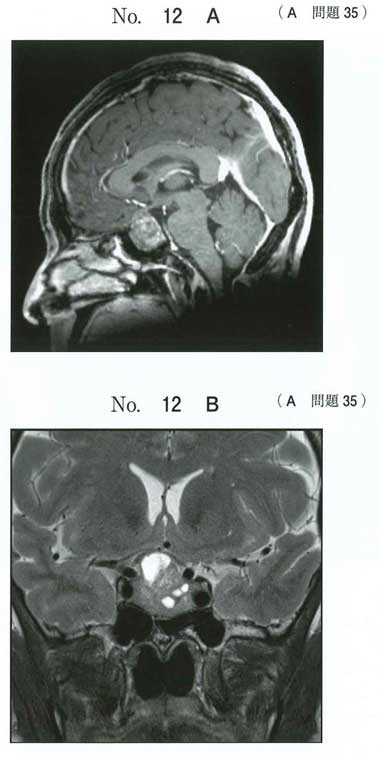

先端巨大症です。

やはり過去問でも頻出の疾患です。